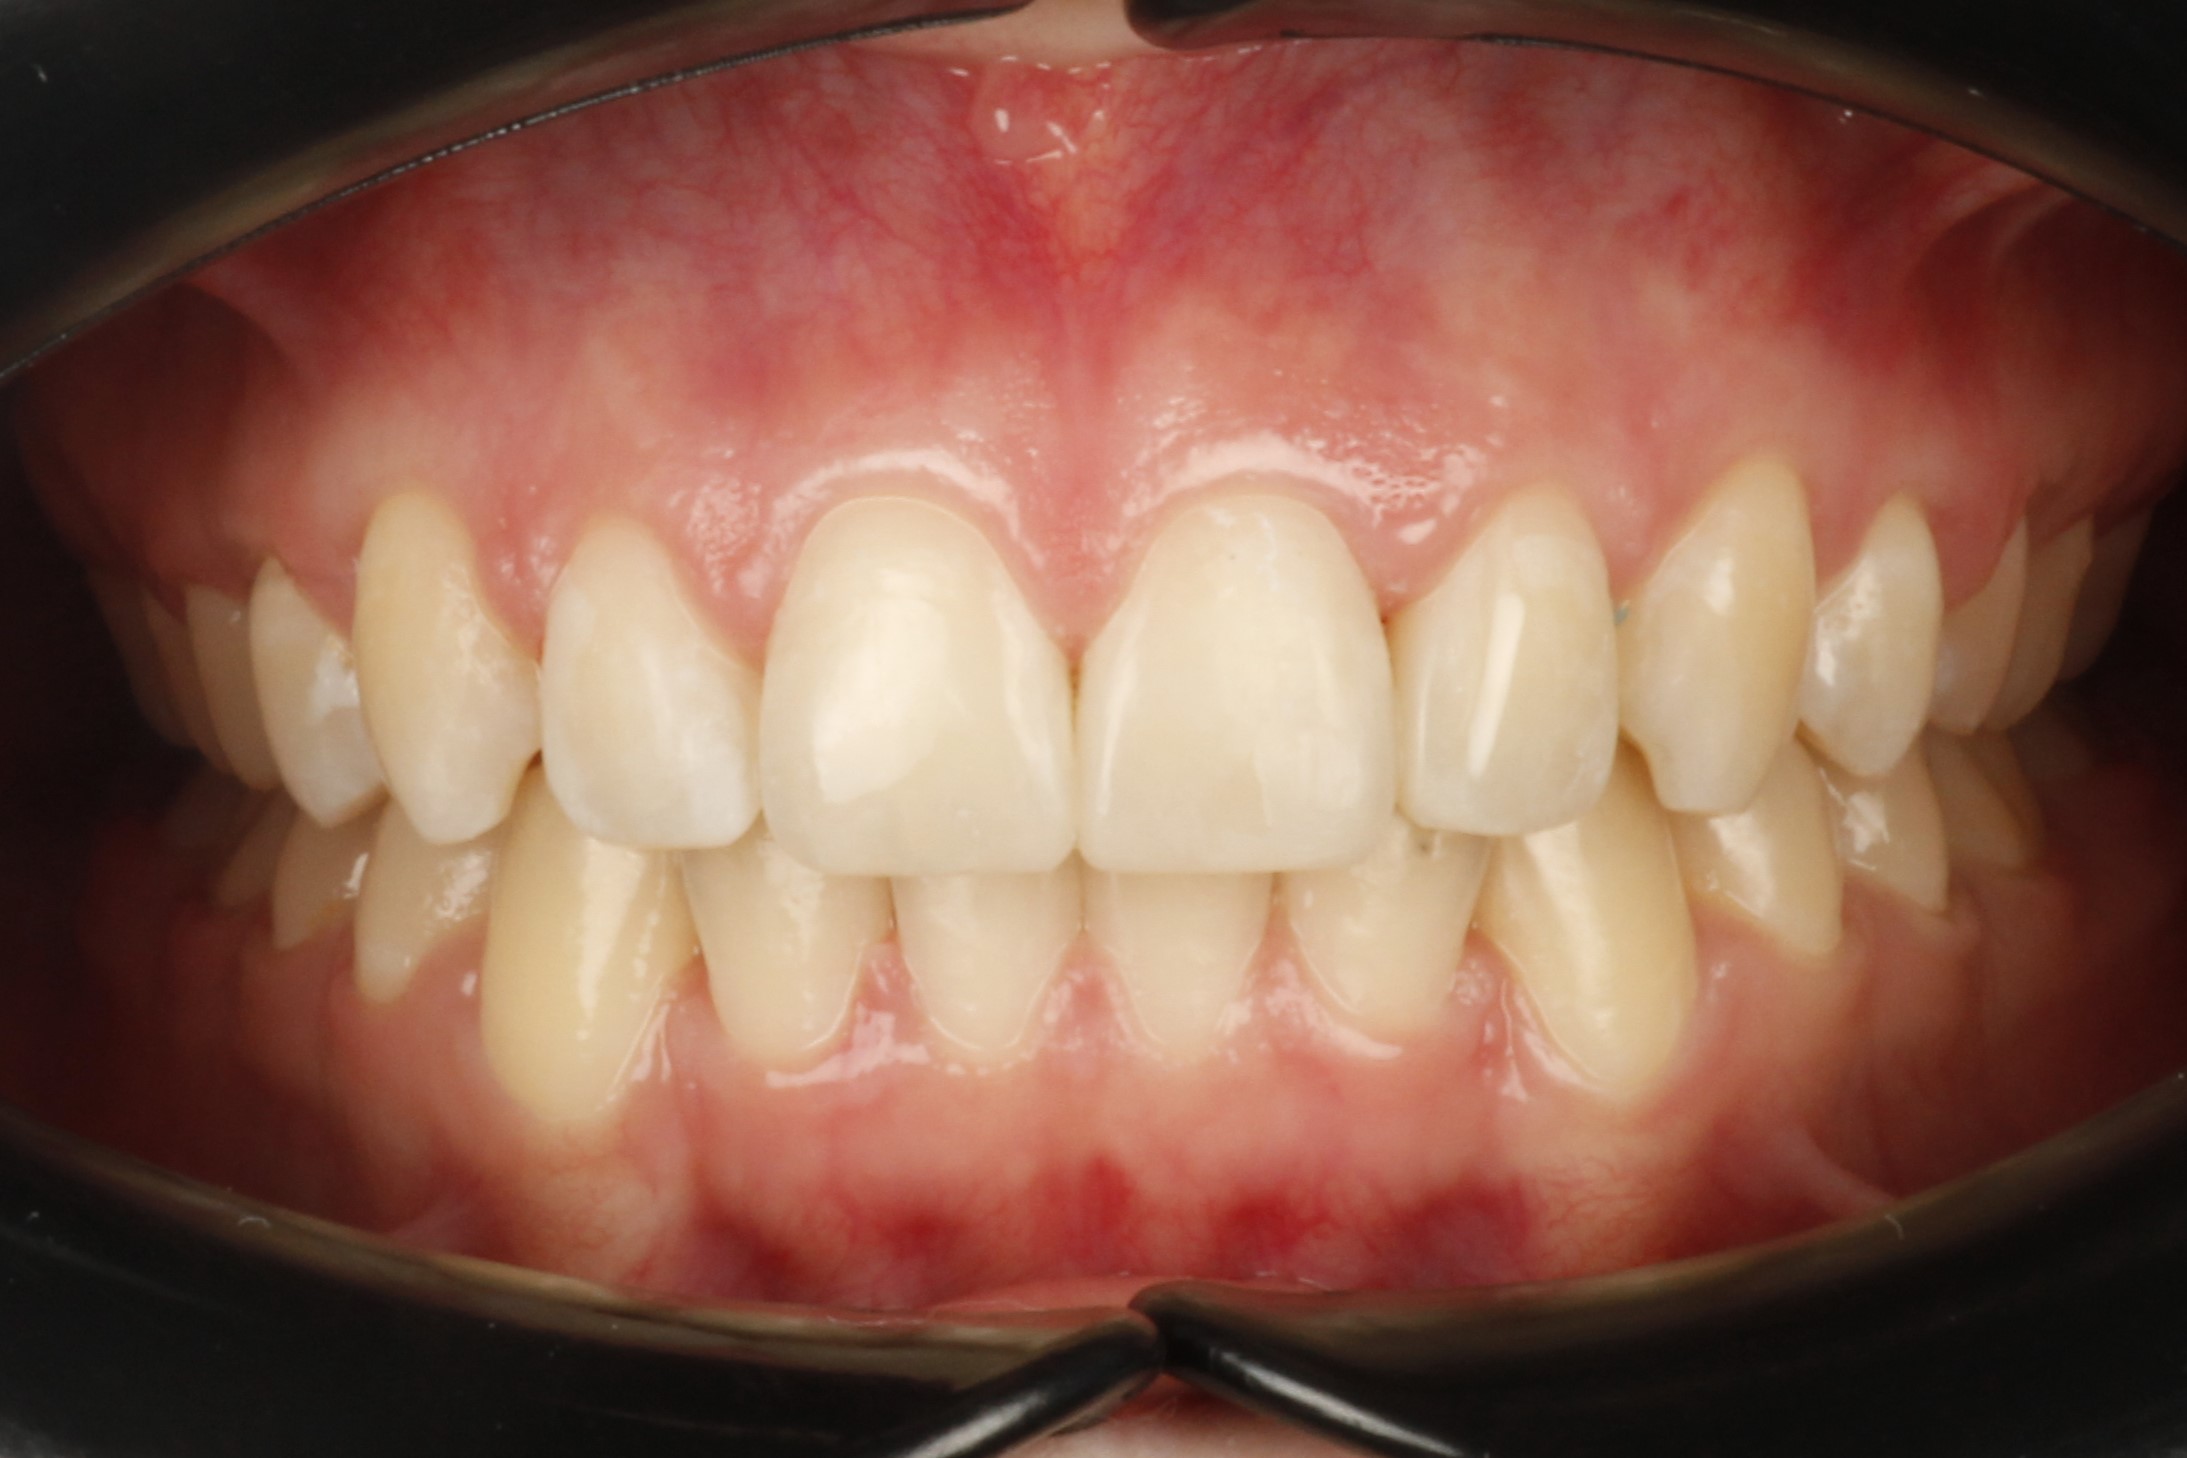

Я такая счастливая!!! Могу улыбаться, не стесняясь!! Спасибо моему ортодонту Ольге Валерьевне и команде клиники ОК!!

Хотела всегда смеяться и не стесняться. Исправлением прикуса в клинике ОК очень довольна! Моя улыбка настолько красива теперь, что я на седьмом небе от счастья

Я всегда мечтала о широкой улыбке, мне не нравился мой наклон зубов. Клиника ОК подарила мне осуществление моей мечты!!

Когда стесняешься улыбаться, то и радости в жизни кажется не так много. Получив свою красивую улыбку, я постоянно теперь нахожу поводы для радости!

Я больше не стесняюсь улыбаться, моя улыбка стала белоснежной, яркой и неотразимой. Спасибо команде «Клиника ОК» за это Чудо!